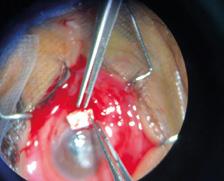

La queratitis ulcerativa periférica (QUP) es una lesión inflamatoria y destructiva del estroma y epitelio corneal yuxtalimbar que lleva a un adelgazamiento progresivo de la córnea. En su etiopatogenia están involucrados desórdenes inmunológicos favorecidos por la vasculatura perilimbar. Muchas veces cursa con escasa sintomatología, por lo que puede llegar a la perforación sin que el paciente sea consciente de ello.

La QUP puede aparecer de forma aislada o estar asociada a una enfermedad sistémica, siendo los síndromes vasculíticos los más frecuentes.

En estos casos, la QUP puede ser la primera manifestación de la enfermedad sistémica siendo la afectación ocular un signo de mal pronóstico ya que expresa actividad de la enfermedad.

La granulomatosis con poliangeitis asociada a ANCA C+ (exenfermedad de Wegener) es una vasculitis granulomatosa necrotizante sistémica, potencialmente letal, que puede afectar los tejidos oculares. En su manejo, son fundamentales el diagnóstico precoz y un tratamiento adecuado.

Paciente masculino de 48 años de edad se presenta en la guardia oftalmológica refiriendo leve dolor y molestias en el ojo izquierdo de aproximadamente 1 mes de evolución. A la anamnesis dirigida, el paciente menciona como antecedente: anemia y nefropatía en estudio.

AVMC: OD: 10/10

OI: 2/10

Bomicroscopia:

OD: inyección conjuntival mixta, úlcera corneal periférica con forma de media luna de horas 7 a 11.

OI: inyección conjuntival mixta, úlcera periférica de horas 12 a 5, con perforación a horas 3, protrusión de iris.

FO: sin particularidades en AO.

Se realiza interconsulta con reumatología y se decide intervención quirúrgica urgente de reparación primaria con parche escleral y recubrimiento conjuntival en OI, y solo recubrimiento conjuntival en OD, que se realiza el mismo día.

Luego de la cirugía, se inicia tratamiento sistémico con meprednisona 40mg/día, vía oral. El paciente presenta buena evolución a las 24 horas de postoperatorio.

En los exámenes de laboratorio solicitados por reumatología, el paciente presenta anemia, proteinuria, microhematuria, ANCA C+, diagnosticándose granulomatosis con poliangeitis asociada a ANCA C+. A los 10 días, el paciente presenta nueva úlcera corneal periférica inferior en OD, por lo que reumatología indica pulsos de metilprednisolona y posteriormente tratamiento inmunosupresor con ciclofosfamida. En los días siguientes evoluciona de forma desfavorable presentado adelgazamiento corneal periférico en AO. Se interviene nuevamente al paciente realizando recubrimiento con membrana amniótica bilateral.

En los controles presenta una evolución favorable con membrana amniótica aplicada que se reabsorbe a los 10 días –aproximadamente– en ambos ojos. Se observa franca mejoría de la superficie, transparencia, espesor e inflamación corneal.

Al mes de la última cirugía, el paciente continúa con enfermedad inactiva, asintomático y córnea en condiciones estables. Se realiza seguimiento por reumatología con tratamiento inmunosupresor mediante pulsos de ciclofosfamida.